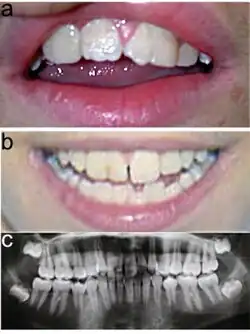

- makrodoncja (100%)

- z oligodoncją (38%)